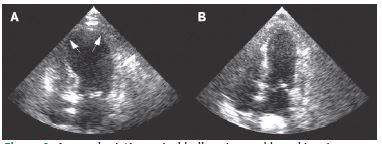

Arterial blood gas analysis revealed metabolic acidosis with elevated lactate levels. A bedside POCUS (Point-of-Care UltraSound) was performed, which showed apical ballooning and apical hypokinesia, indicating left ventricular dysfunction with an ejection fraction of 40%, later confirmed by the cardiologist (Figure 5).

Figure 5: Apical ballooning with hypokinesia in apical 4-chamber view.